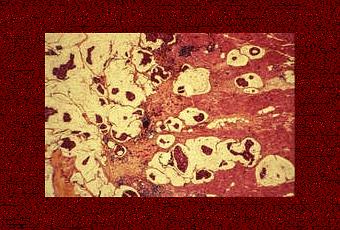

Carcinome bien différencié, cancer canalaire invasif (x250)

Source iconographique et légendaire: http://www.inserm.fr/dossiers-d-information/cancer-du-sein